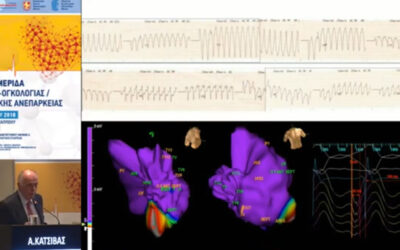

Στο βίντεο μας μιλούν για το νέο Κέντρο Καρδιάς και Αγγείων «Athens Heart Center» στο Ιατρικό Π. Φαλήρου ο κ. Ιωάννης Πυρνοκόκης, Γενικός Διευθυντής και ο δρ Απόστολος Κατσίβας, Καρδιολόγος- Αρρυθμιολόγος, Διευθυντής.